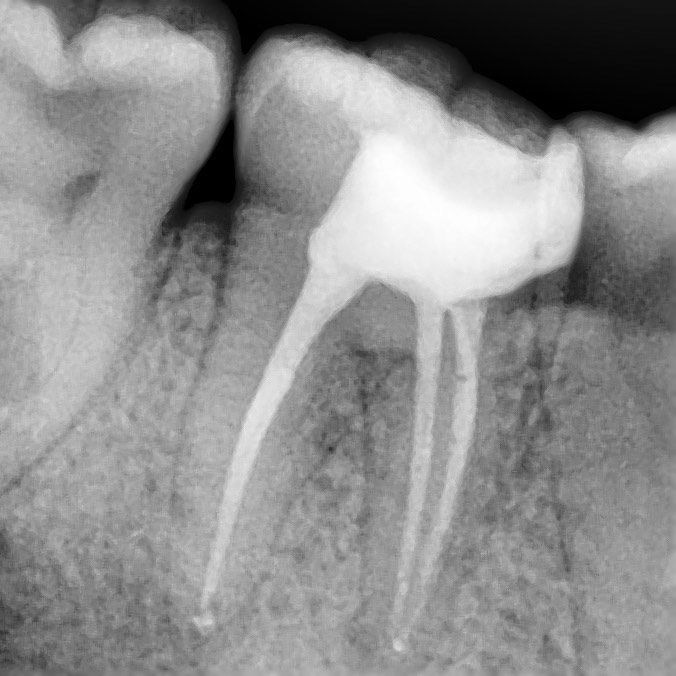

точное определение формы каналов

Высокоточный рентген показывает форму каналов и область воспаления

контрольный рентген